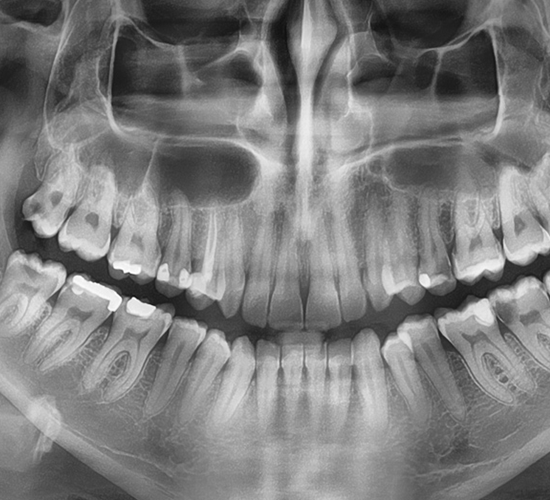

Radiografie dentara digitală:

Radiografia dentară digitală este extrem de utilă în diagnosticarea unei afecțiuni dentare, oferindu-i medicului o unealtă extrem de precisă în detalii și măsurători pe baza cărora medicul poate evalua cantitatea și calitatea structurii osoase, poate vedea structuri anatomice precum nervii sau sinusurile maxilare.

Radiografia dentară intraorală periapicală prinde pe filmul digital întregul dinte de la coroană, până la rădăcină și țesuturile osoase de suport. Radiografia dentară periapicală ne ajută să identificăm anomalii la nivelul rădăcinii și a structurii osoase a dintelui.